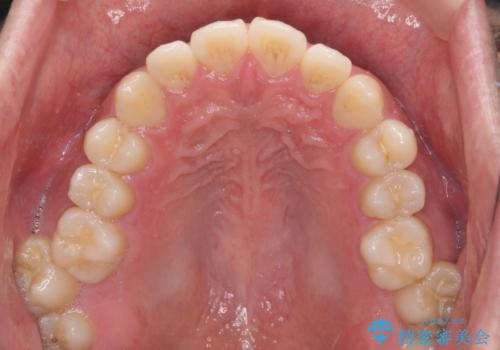

インビザラインで奥歯の咬み合わせと前歯のデコボコを改善

- 前歯のデコボコと奥歯の咬み合わせを気にして来院された患者様です。

前歯のデコボコはインビザラインで十分に対応可能と判断できましたが、咬合力が強いため、臼歯(特に右側)の交叉咬合はインビザライン単体では困難と思われました。

まずはインビザライン単体で矯正治療を開始し、交叉咬合が改善されない場合にはアンカースクリューなどの使用を検討することとしました。

インビザライン単体では右側の交叉咬合を解消することができなかったため、アンカースクリューを併用して咬合を改善させました。